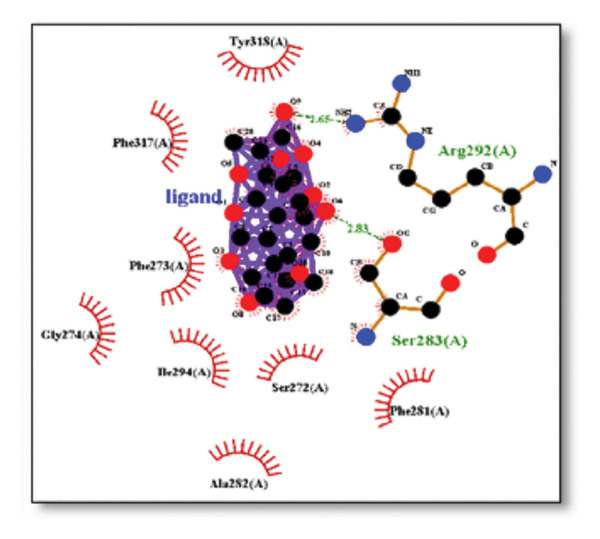

The sortilin receptor demonstrated the highest affinity for ginkgolide (−16.29 kcal/mol), representing the strongest binding observed across all targets. Key interactions for ginkgolide involved hydrogen bonding with ARG292 and TYR318. Other strong binders included ginsenosides (−8.07 kcal/mol) interacting with ILE141 and MET139 and dronabinol (−7.91 kcal/mol); for instance, 4‐tert‐amylphenol formed highly favorable bonds with ARG292 (donor–acceptor D–A distance: 2.92, angle Ǻ and 3.11 Ǻ:164.68°, Figure 2 details the binding characteristics of all tested ligands. Table 2 shows the predicted hydrogen bond interactions for selected molecules and drugs against sortilin, clusterin, amyloid, and tau proteins.

The in silico predictions for ginkgolide’s interactions with sortilin, clusterin, and tau are well‐supported by the established structural and functional mechanisms of these proteins in scientific literature. For sortilin, the predicted interaction with ARG292 and TYR318 is consistent with the protein’s known structure. Studies have shown that its large, ten‐bladed β‐propeller domain is the primary ligand‐binding site; ARG292, often positioned near the VPS10P domain, likely provides critical electrostatic stabilization, while TYR318 contributes $\pi‐\pi$ or $\pi$‐cation interactions, collectively stabilizing the ligand–receptor complex. This binding site overlaps with regions known to undergo conformational change during ligand recognition, suggesting ginkgolide may allosterically modulate the receptor’s trafficking function. A 2017 study by [ref. 38], for example, demonstrated how conformational changes in this domain, caused by pH, disrupt binding sites. Similarly, a review by Quistgaard et al. [ref. 39] highlights how the architecture of the VPS10 domain, which includes these residues, is vital for its function. For clusterin, the predicted interaction with HIS205 is supported by the protein’s established role as a molecular chaperone that prevents protein aggregation.